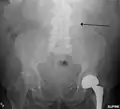

The faint outline of the calcified wall of an AAA as seen on plain X-ray

An abdominal aortic aneurysm is usually diagnosed by physical exam, abdominal ultrasound, or CT scan. Plain abdominal radiographs may show the outline of an aneurysm when its walls are calcified. However, the outline will be visible by X-ray in less than half of all aneurysms. Ultrasonography is used to screen for aneurysms and to determine their size if present. Additionally, free peritoneal fluid can be detected. It is noninvasive and sensitive, but the presence of bowel gas or obesity may limit its usefulness. CT scan has nearly 100% sensitivity for an aneurysm and is also useful in preoperative planning, detailing the anatomy and possibility for endovascular repair. In the case of suspected rupture, it can also reliably detect retroperitoneal fluid. Alternative less often used methods for visualization of an aneurysm include MRI and angiography.